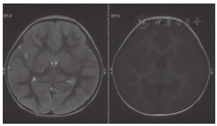

患儿,男,2岁5个月时因"间断呕吐、腹泻、昏迷及嗜睡1年余"就诊。患儿1岁3个月内发育正常,1岁3个月时进食大量甜瓜,1 d后呕吐、腹泻、腹痛,当地医院考虑肠套叠,经气灌肠治疗后好转。平素厌食水果及甜食,自述吃水果后腹痛,喜欢肉类、蛋、粮食。患儿1岁3个月~2岁1个月间断呕吐发作4次,伴腹泻、嗜睡、昏迷及肝损害,进食水果后或患上呼吸道感染时发作,伴酸中毒,血pH低至6.9,未检测血糖,每次发作时经葡萄糖、碳酸氢钠等静脉输注后病情很快缓解。外院血氨基酸、酯酰肉碱谱及尿有机酸分析结果大致正常。发作间期无异常。患儿于2岁5个月时进食较多水果,30 min后出现呕吐,昏迷,抽搐。当地医院检测发现低血糖(0.52~2.30 mmol/L,正常参考值3.61~6.11 mmol/L),代谢性酸中毒,血乳酸增高(2.2~15.9 mmol/L,正常参考值0.5~2.0 mmol/L)。尿酮体阳性,尿蛋白微量。血清电解质正常,丙氨酸转氨酶(ALT)增高(78~123 IU/L,正常参考值0~40 IU/L),天冬氨酸氨基转移酶(AST)增高(94~154 IU/L,正常参考值0~45 IU/L)。头颅CT、磁共振成像(MRI)显示弥散性脑水肿、尾状核、苍白球及壳核肿胀(图1、图2),可见广泛血管炎性水肿及细胞毒性水肿,符合低血糖脑病。静脉滴注葡萄糖、碳酸氢钠、甘露醇及保肝药物后一般情况好转,但此后睡眠中时有抽搐,为局灶性发作,四肢肌张力增高,伴痉挛型瘫痪。

饮食治疗原则为限制果糖摄入,避免食用水果、奶类、南瓜、动物肝脏及胡萝卜,鼓励肉、蛋、豆类、鱼虾、粮食及菜类等食物,避免长时间饥饿。为缓解肌紧张,口服盐酸苯海索片及氯硝西泮。为保证营养,给予左卡尼汀、维生素B12、A、D等支持治疗。治疗后1个月后复查脑MRI显示侧脑室扩张,提示脑萎缩(图4)。随访至3岁,智力逐渐恢复,痉挛型截瘫逐渐好转,治疗后未再出现呕吐、腹痛及抽搐等症状。

Baker和Winegrad[7]于1970年首次报道本病,迄今全球已报道100余例[1,2,6,7,8]。患者临床表现缺乏特异性[9],多于长时间饥饿、发热、进食大量果糖或饮酒后出现急性代谢紊乱,亦可进食百里香后起病[10]。患儿多于2岁内起病[5],其中约50%为出生后1~4 d出现症状,因严重乳酸酸中毒及低血糖导致过度通气。最早于出生后数小时发病,表现为新生儿低血糖症,由于糖原贮存不足,预后多数不良。亦可晚至成年期发病[1],并逐渐出现易激惹、嗜睡、昏迷、呼吸困难、心动过速、肌张力低下及肝大等症状。本例患儿的临床表现与国外报道病例类似,在进食大量水果及急性感染后出现酮症性低血糖及乳酸酸中毒,遗留痉挛型截瘫等神经系统后遗症,既往文献中未见有患儿相关影像学报道,本研究报道了果糖-1,6-二磷酸酶缺乏症低血糖脑病后继发性痉挛型瘫痪患儿的头颅影像学变化。